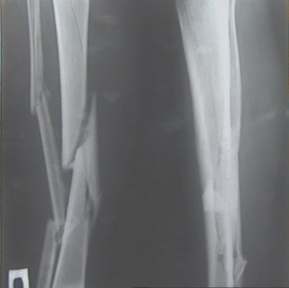

Неправильно сросшийся перелом голени

Уважаемые коллеги! На консультации больной предъявляет жалобы на хромоту (укорочение - 2см), боль в месте перелома при нагрузке (спортсмен).

Семь месяцев назад получил закрытый перелом, лечился консервативно в одной из больниц города. Как-бы кто лечил? Сам склоняюсь к LCP с костной пластикой.

Юрий Алексеевич, привет. А перелом то вроде сросся! -правда с варусом - угол можно посчитать у Вас по снимкам (в письме - суставов нет в прямой проекции). Я бы не спешил, с открытой хирургией тем более. Риски велики. Укорочение абсолютное тоже мизерно. А коррекцию оси сделал бы попозже малоинвазивным методом по Илизарову ГА.